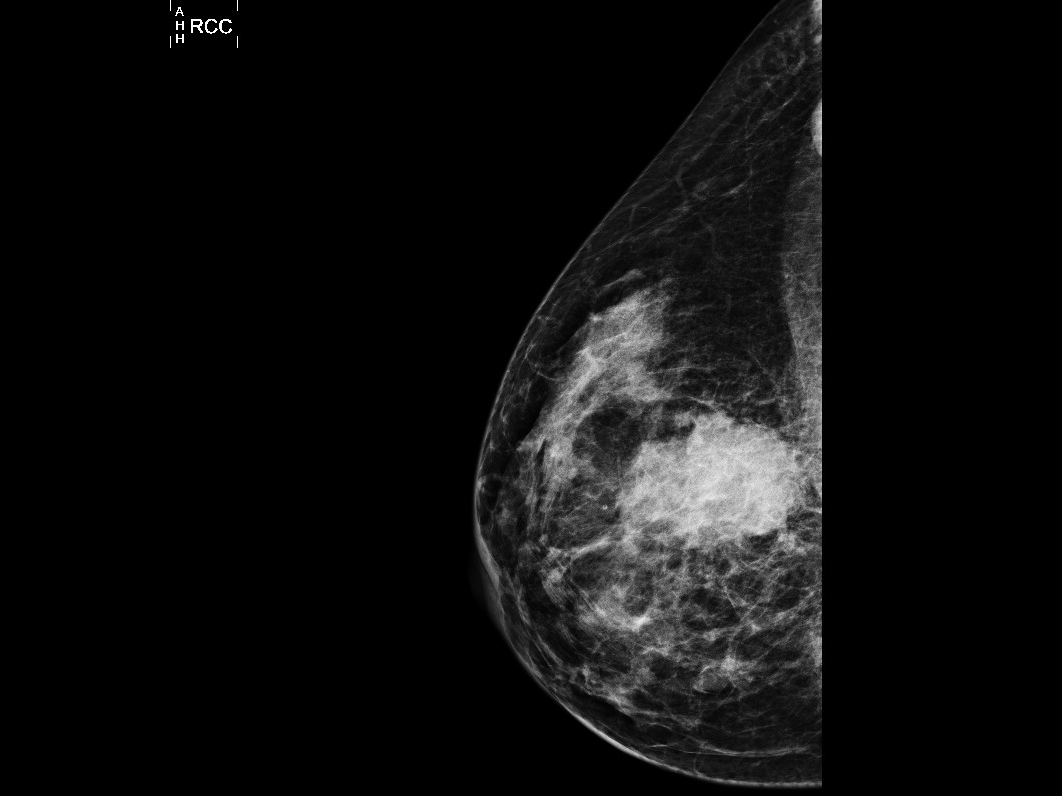

Estudios de imagen

La importancia de este tipo de estudios está en identificar características del tejido mamario también el identificar la extensión de la enfermedad. Algunos de los más usados son:

- Mastografía. Estudio de rayos X que permite obtener una imagen bidimensional de la mama para su valoración e identificación de anomalías o tumores.